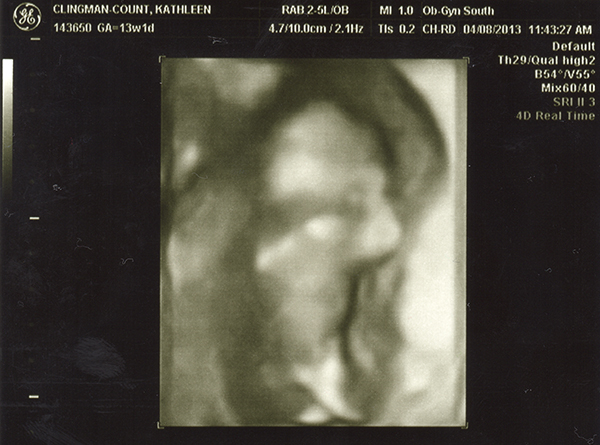

I had an ultrasound on Monday -- 13 weeks. I don't feel as though any of these are very clear pics. Even if they were better, I still wouldn't be any good with ultrasounds! Any of you experts able to make anything out with these? The tech guessed boy but the picture is not clear to me at all! She also kept saying the cord was between baby's legs and that we shouldn't go out and buy anything blue just yet. Any hope that it's a girl??

Attachment 10495